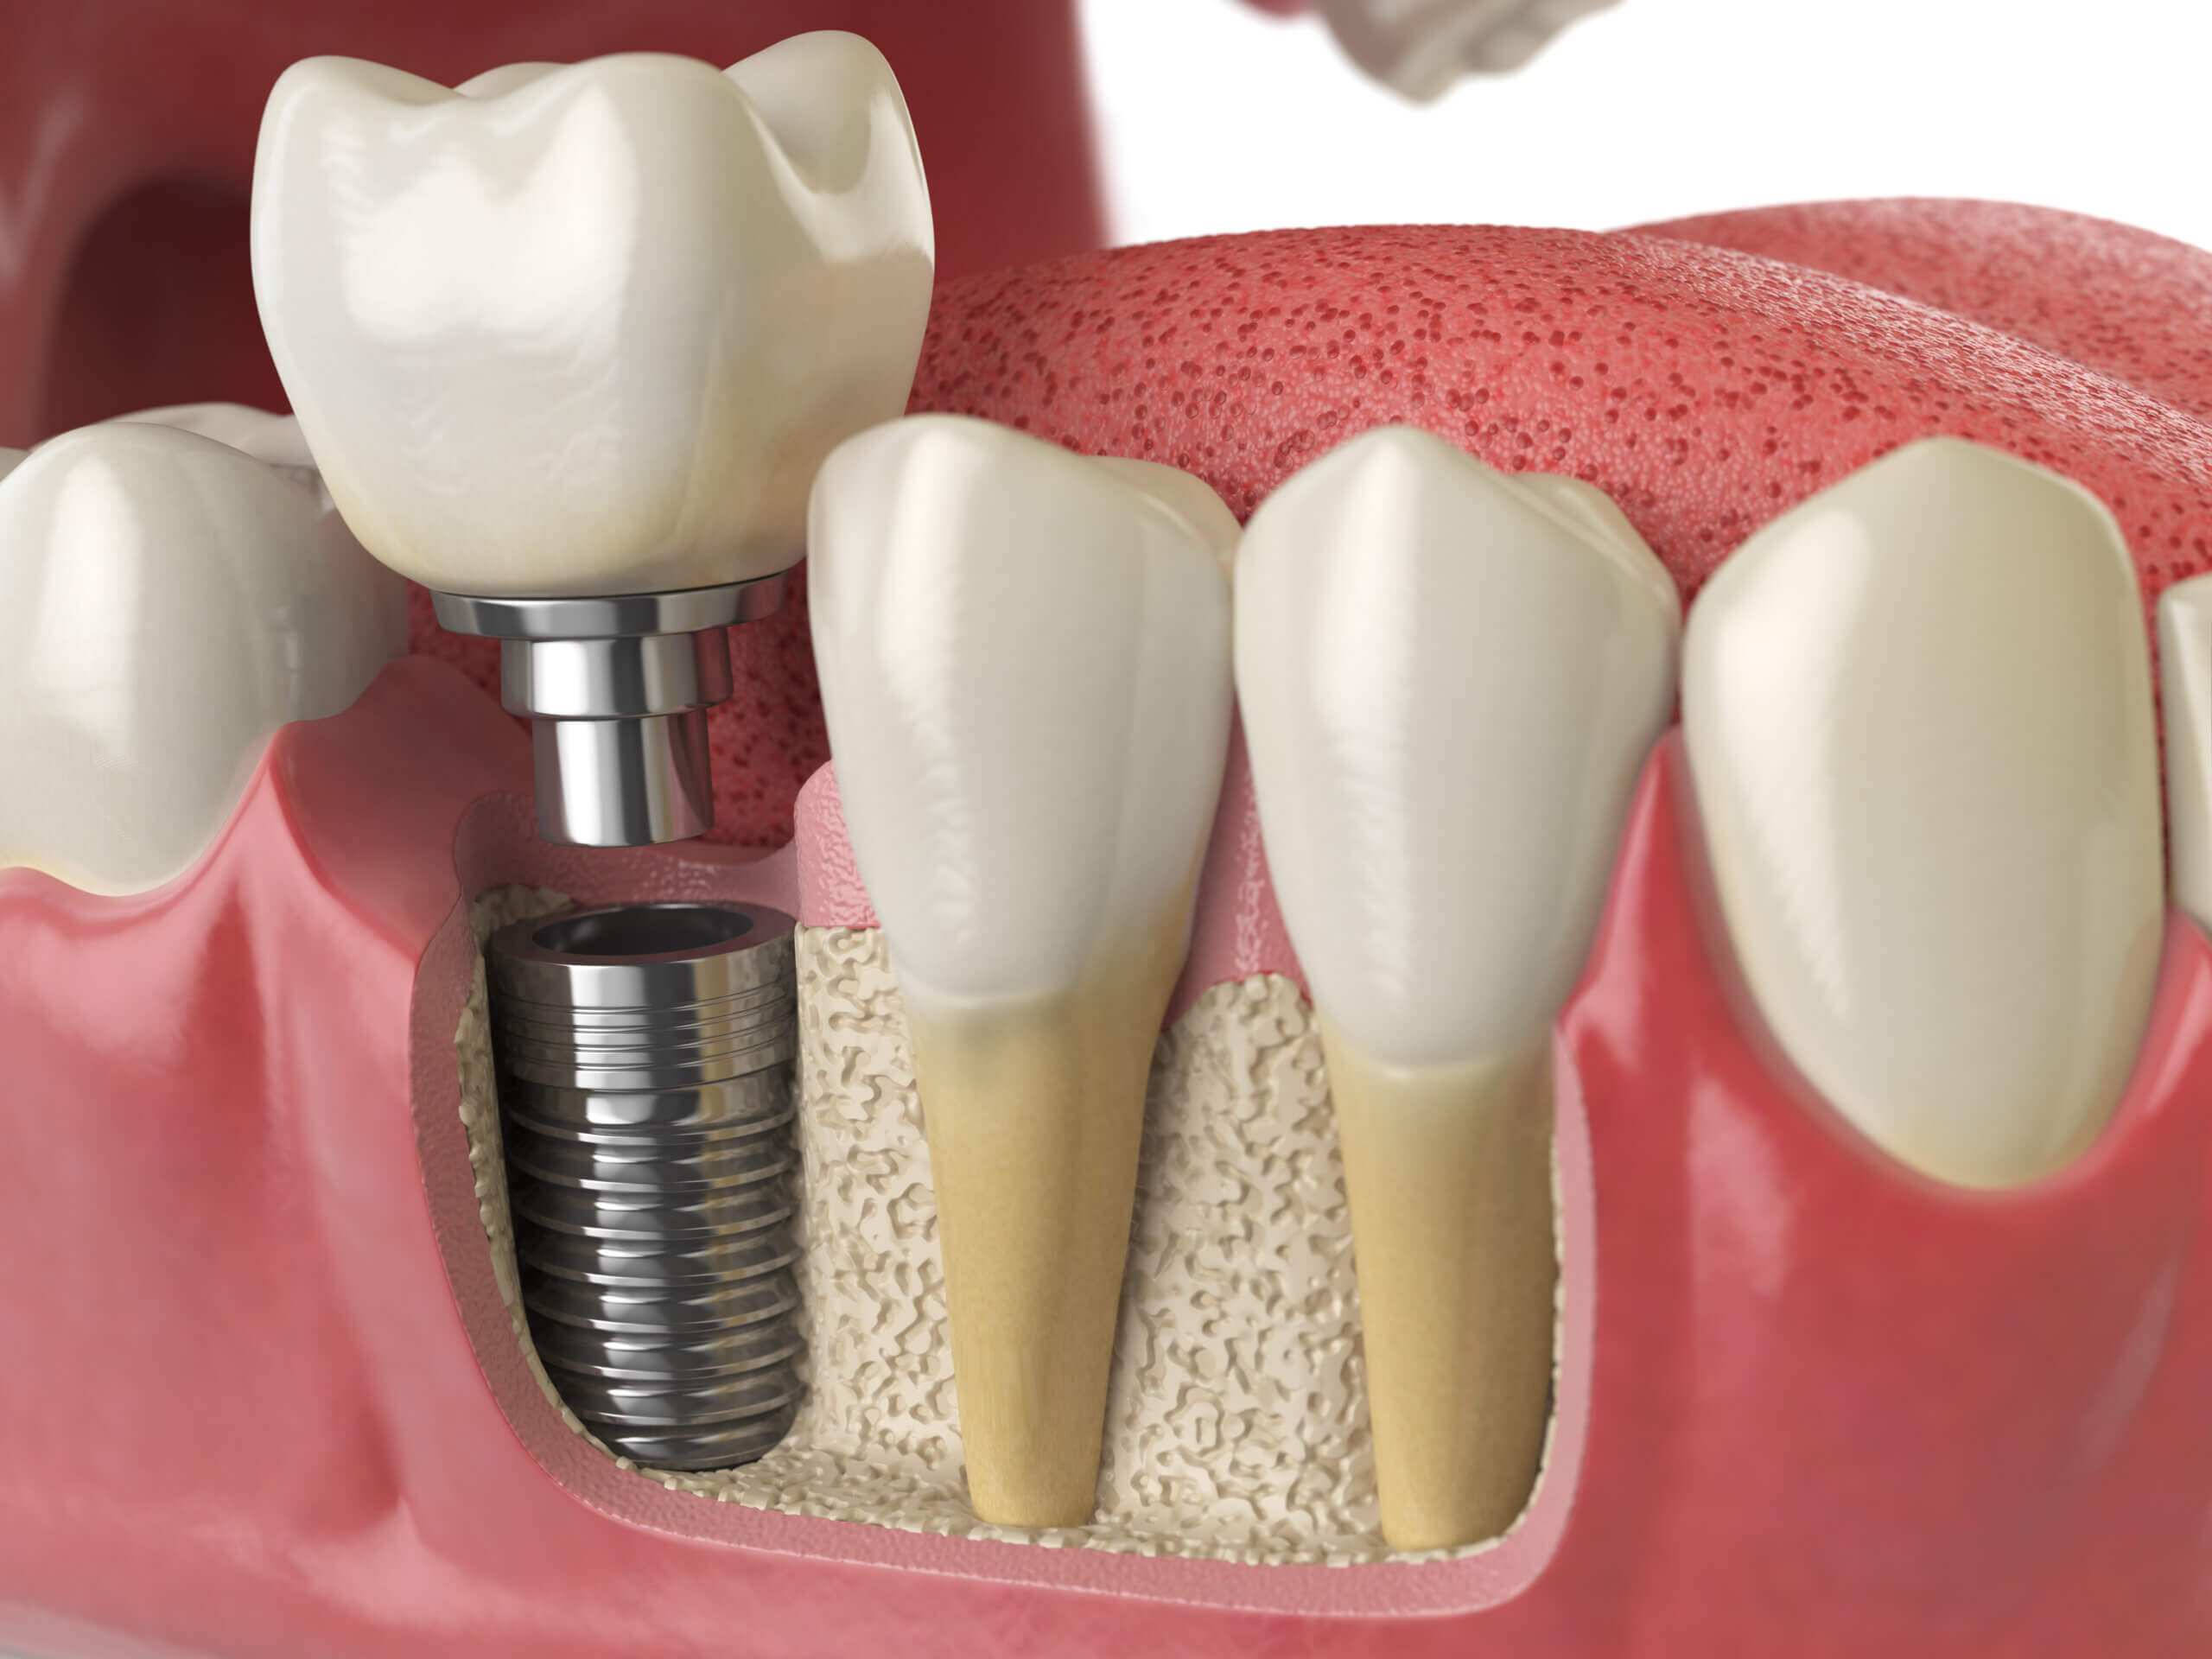

Grand Parkway Smiles is a multi-specialty dental implant, oral surgery, and general dentistry center in Katy, TX. Near Cinco Ranch. Our dental specialists have a combined 120+ years of experience including Dr. Ryan Smart oral surgeon, Dr. David Gomez dental implantologist, Dr. Louis Bosse prosthodontist, endodontist, and pediatric dentist—provides comprehensive, pain-controlled care under one roof. Services include dental implants, All-on-4 and snap-in dentures, wisdom teeth removal, root canals, extractions, full-mouth restoration, TMJ/TMD care, cosmetic dentistry, and IV sedation for anxiety or complex procedures. Same-day emergency visits available. We accept most PPO dental insurance and offer in-house payment plans and financing.